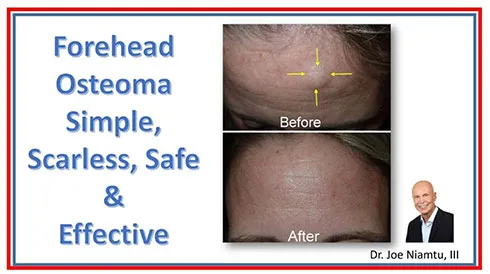

These non-mobile lumps of bone are generally benign and cause no specific problems other than cosmetic concern. It is interesting that some patients live with this condition for years because they don’t realize that the treatment is generally a simple office procedure.

The treatment can frequently be performed with endoscopic technique through a button hole incision. It can be performed with local anesthesia, but due to the instrumentation required to remove the lump and smooth the bone, IV sedation is preferable.

Forehead osteomas can also be treated with an open technique where the incision is hidden in the hairline.

The images below show selected before and after cases of endoscopic osteoma removal.